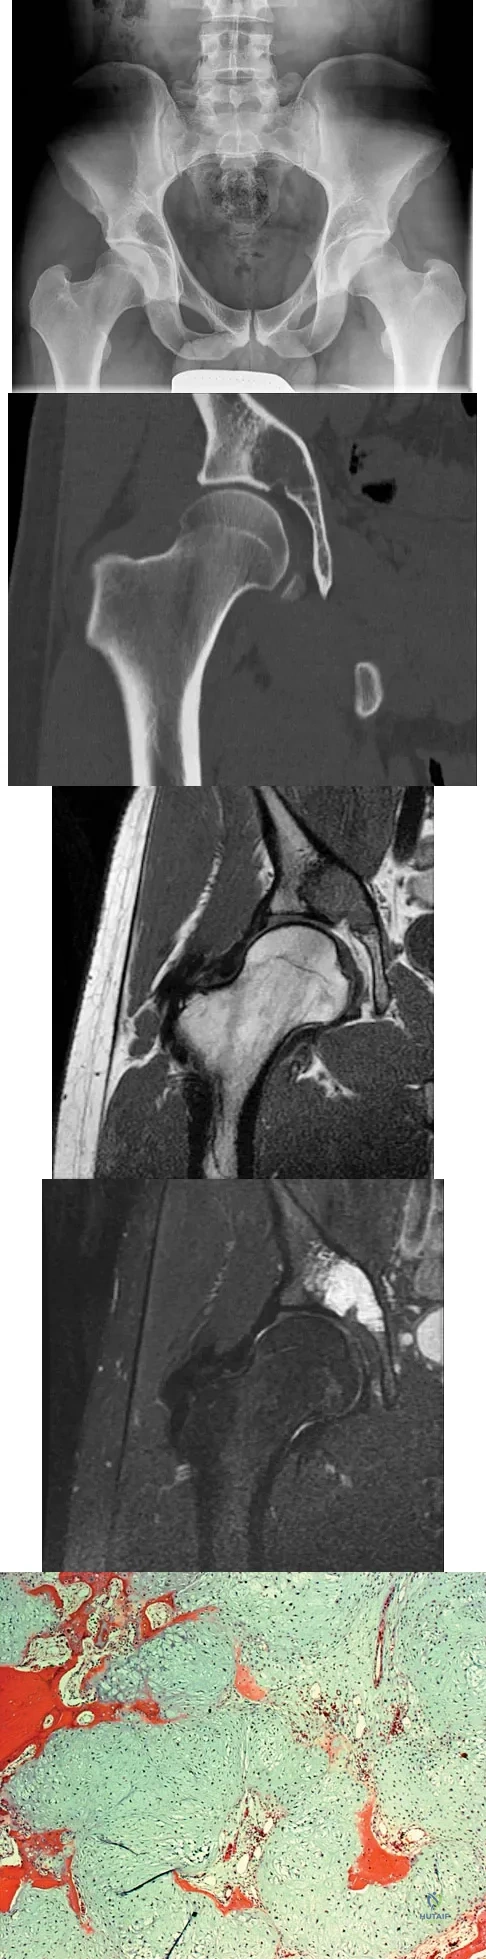

Question 62

A 21-year-old man has had right groin pain for the past year. A radiograph, CT scan, MRI scans, and a biopsy specimen are shown in Figures 50a through 50e. What is the most likely diagnosis?

Explanation

A 57-year-old man reports right hip pain that has been progressive for the past several months. The pain is exacerbated by weight-bearing activities and improves somewhat with rest. A radiograph is shown in Figure 10a and a coronal T1-weighted MRI scan is shown in Figure 10b. What is the most likely diagnosis?

Explanation

Question 80

A 44-year-old woman has bilateral knee pain, and history reveals bilateral hip replacements. Radiographs are seen in Figure 28a, and histopathologic specimens from the total hip replacement are shown in Figures 28b and 28c. Laboratory studies reveal anemia. What is the most likely diagnosis?

Explanation